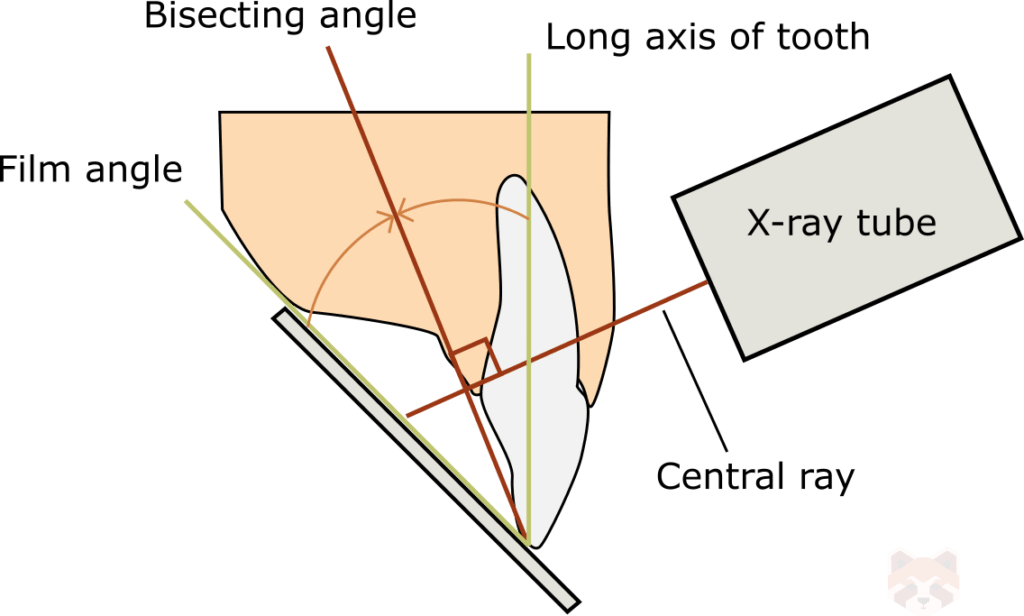

Foreshortening is when the radiographic image appears shorter than the actual object being radiographed. The only way this can happen is if the central ray and image receptor are perpendicular, and the object being radiographed is angled.

Elongation is when the radiographic image appears longer than the actual object being radiographed. There are several situations where this can happen:

- If the central ray is perpendicular to the object, but the film is angled.

- If the object is parallel to the film, but the x-ray tube is angled.

- If the x-ray tube is off-center but perpendicular to the object (beam divergence).

The most commonly used and preferred (most accurate) radiographic technique is the paralleling technique, where the film is held parallel to the long axis of the tooth, producing the most accurate 2D representation of the object. However this is not always possible, likely due to anatomical restrictions. The bisecting angle technique is used as a compromise, where the central ray is oriented perpendicular to the bisecting line made from the angle of the film to the object. Using this technique will keep distortion to a minimum.